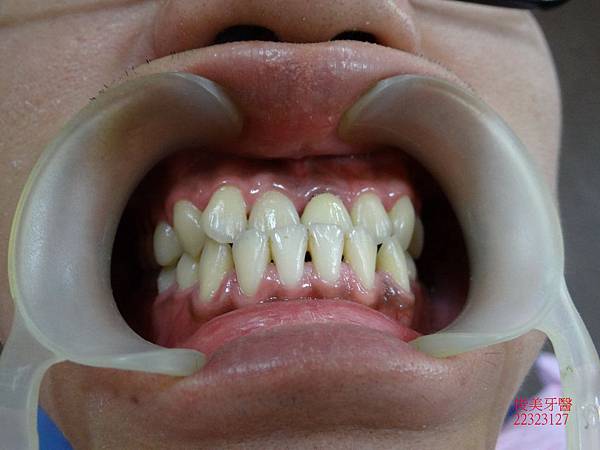

下顎牙弓形狀

咬合狀況。

上排牙明顯被下排牙齒限制住。